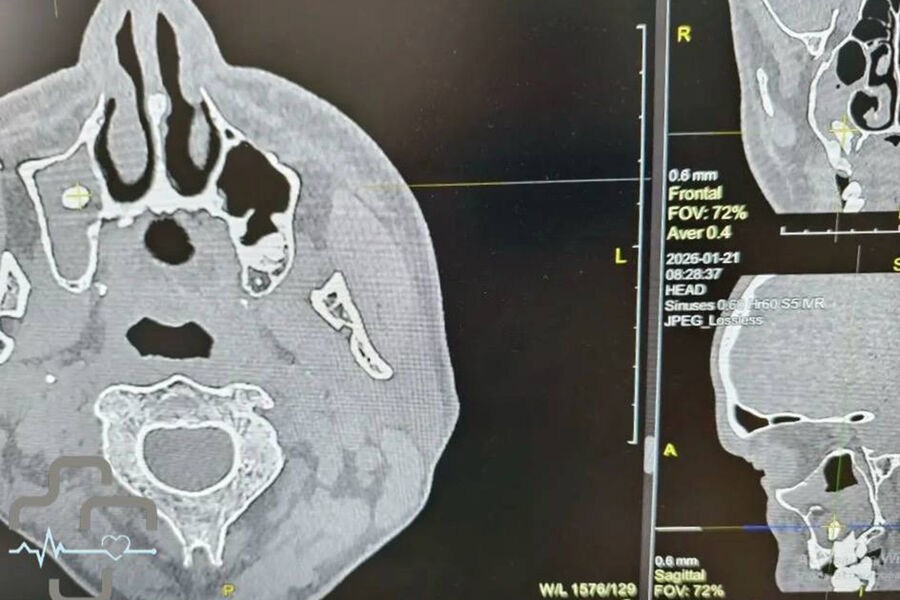

В Орске врачи обнаружили зуб в носовой пазухе у мужчины, который обратился в больницу с жалобами на затрудненное дыхание. Об этом сообщает городская больница Орска.

Диагностика показала, что в правой носовой пазухе мужчины находится зуб. Мужчина вспомнил, что незадолго до этого удалял зуб у стоматолога. Как пояснили врачи, во время процедуры могла нарушиться целостность костной перегородки между зубным рядом и пазухой, из-за чего зуб или его фрагмент сместились внутрь.